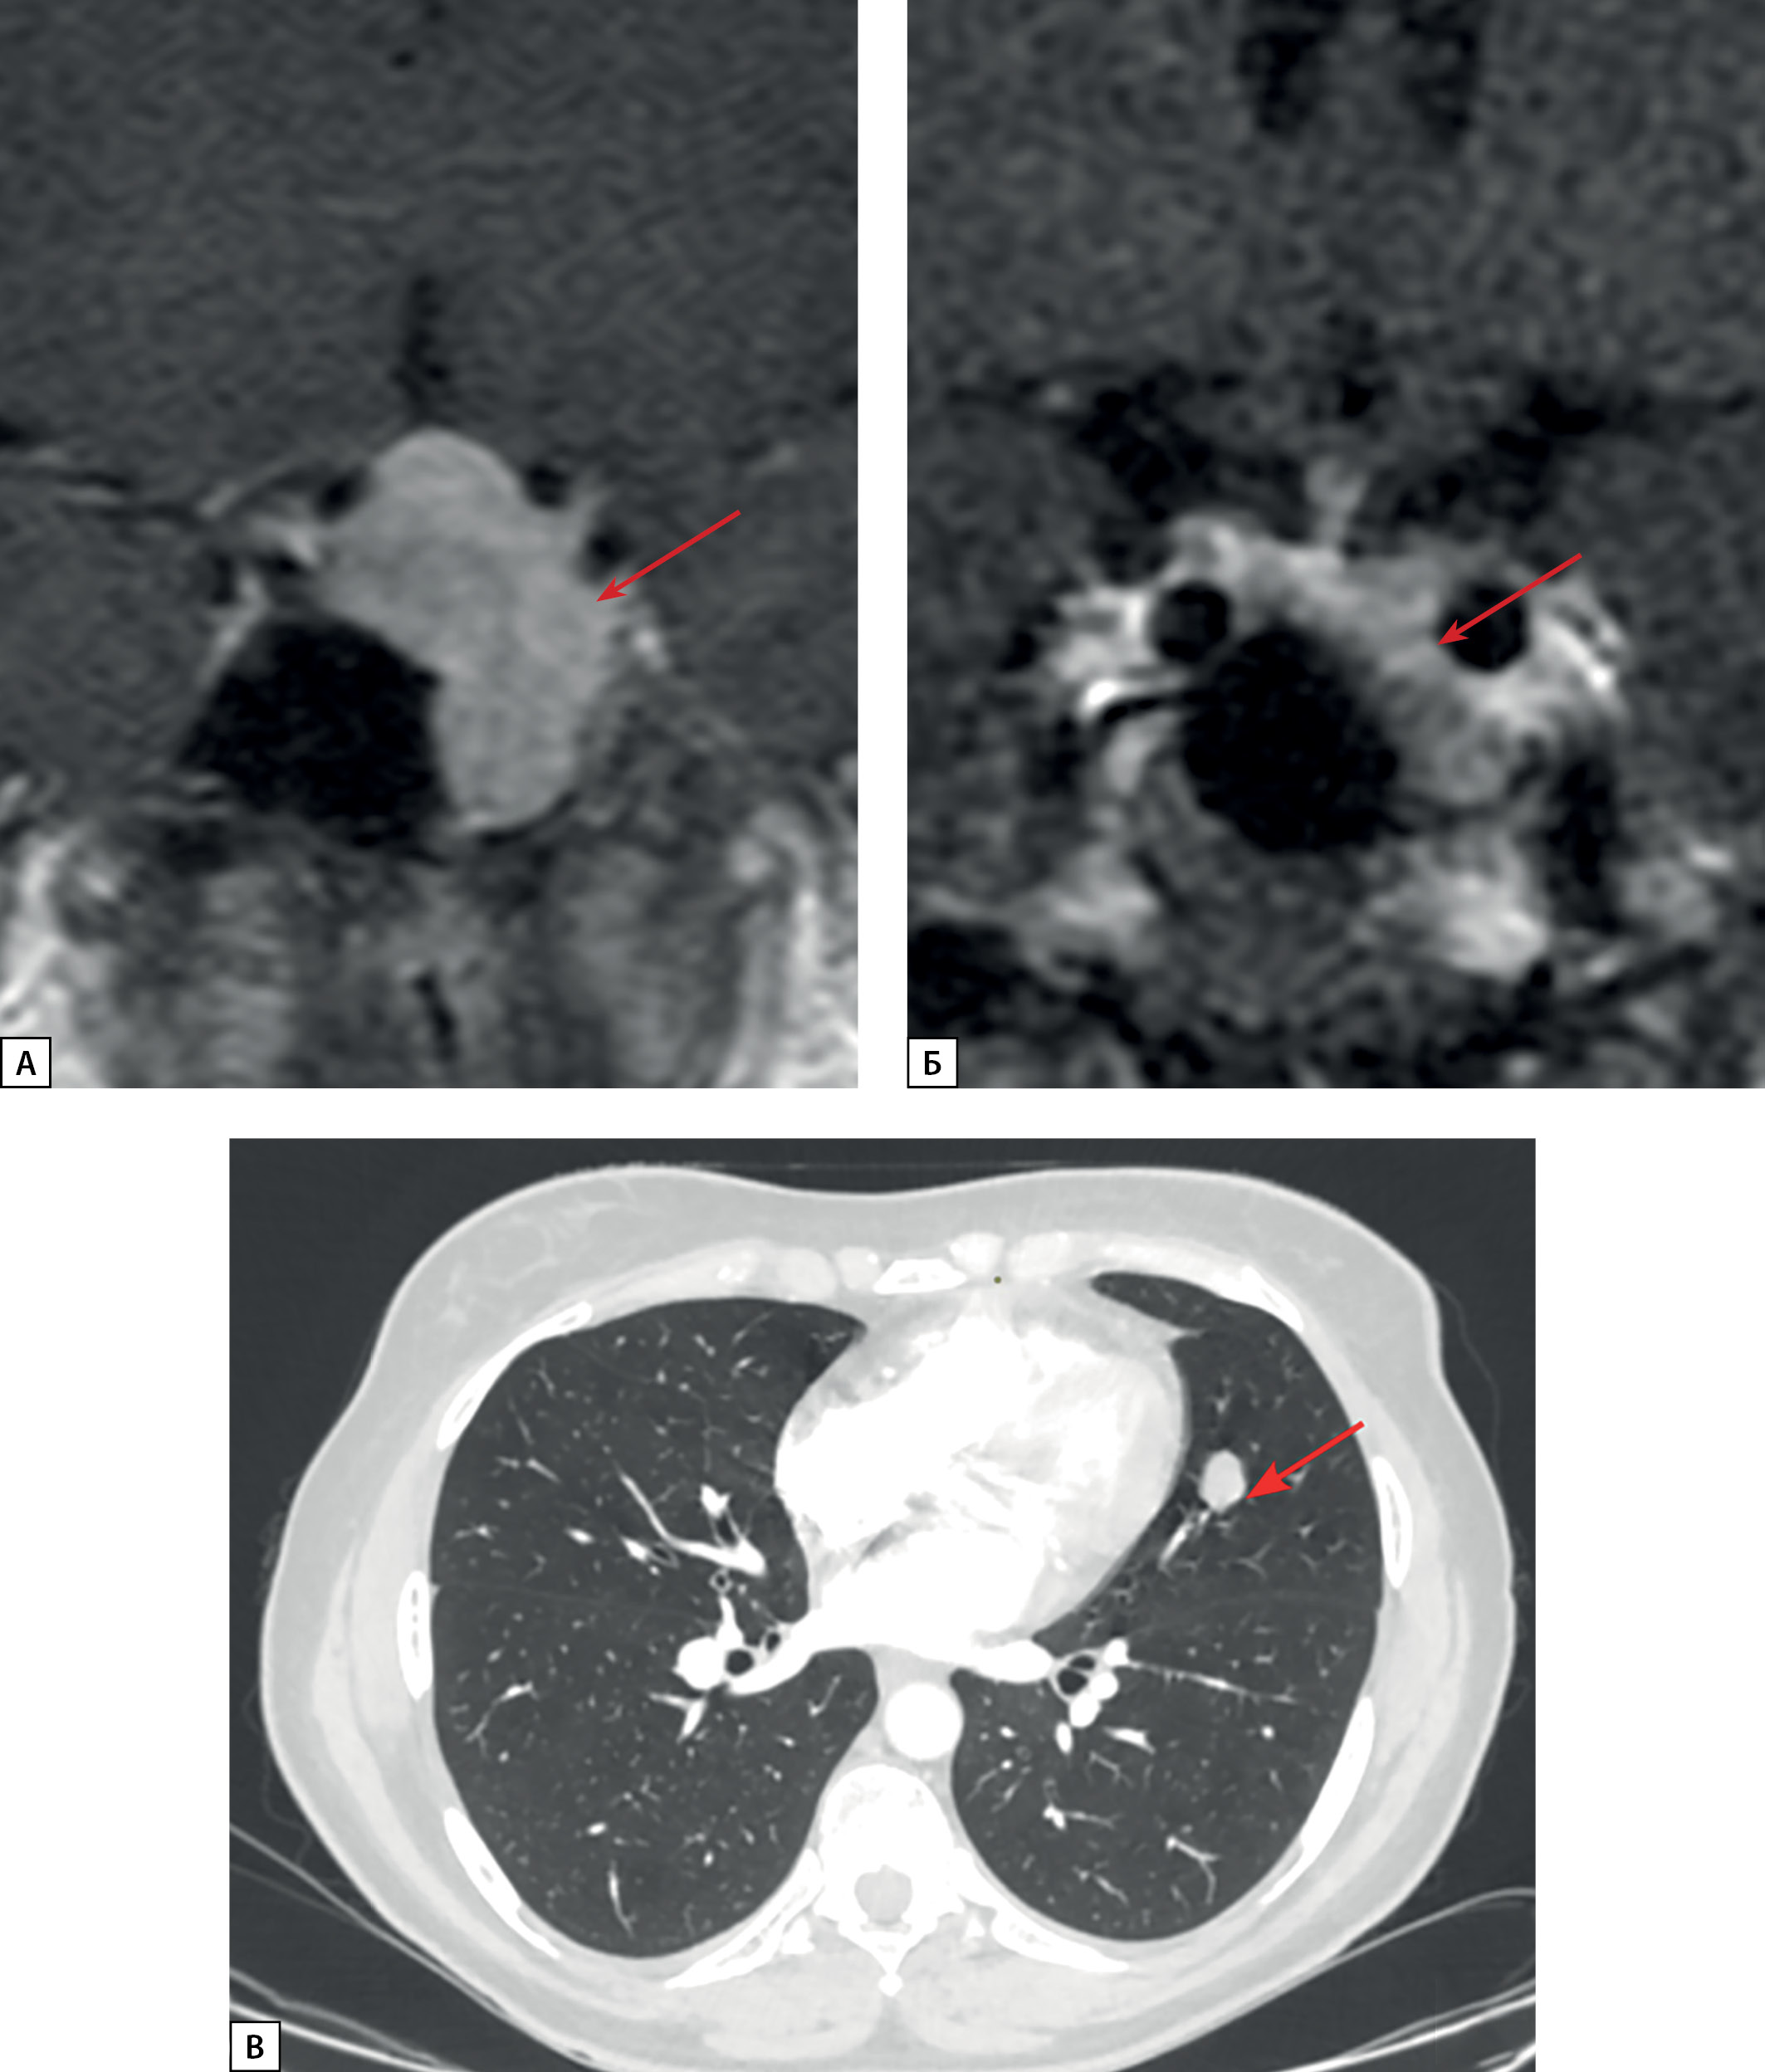

Рисунок 4. МРТ и КТ исследования пациентки Д.И.Е.

а) МРТ гипофиза, корональная проекция, Т1 ВИ с контрастным усилением.

Киста кармана Ратке (стрелка).

Зона слабо сниженного накопления контрастного препарата

в левом отделе аденогипофиза (длинная стрелка);

б) Киста кармана Ратке (стрелка).

Диффузно сниженный МР сигнал на Т2 ВИ от ткани аденогипофиза;

в) МСКТ легких, легочный режим, нативная фаза, аксиальная проекция.

Нейроэндокринная опухоль в S10 левого легкого (короткая стрелка);

г) МСКТ легких, легочный режим, нативная фаза, аксиальная проекция.

Образование в S3 левого легкого с внутри- и перибронхиальным

распространением — очаг отсева (толстая стрелка).

Пациентка Д.И.Е. 1959 г.р., впервые госпитализирована в ГНЦ РФ ФГБУ «НМИЦ эндокринологии» Минздрава России в возрасте 60 лет с жалобами на выраженную общую слабость, головные боли, боли в суставах, потливость, снижение массы тела, отеки лица. Пациентка считала себя больной в течение последних двух лет, когда при обследовании после перенесенного гриппа было выявлено повышение глюкозы в крови до 9,3 ммоль/л, в последующем показатели гликемии нормализовались и была рекомендована диетотерапия. В связи с общим недомоганием пациентка обратилась к эндокринологу по месту жительства, и при обследовании было выявлено повышение уровня ИФР-1 до 349 нг/мл (норма до 200). По МРТ головного мозга отмечалась выраженная неоднородность структуры аденогипофиза слева, где нельзя было исключить аденому гипофиза. Центрально отмечалась гиперинтенсивная на Т2 ВИ структура размерами 3,8х1,5 мм, не накапливающая контрастный препарат (киста кармана Ратке). МР сигнал от аденогипофиза был нерезко снижен на Т2 ВИ (рис. 4 а, б).

В возрасте 61 года пациентка перенесла новую коронавирусную инфекцию, и при проведении МСКТ органов грудной клетки в S10 левого легкого было выявлено объемное образование неправильной формы с четкими, полицикличными контурами размерами 32х32 мм, плотностью 34 ед.Н (рис. 4 в, г). Образование располагалось в просвете заднего базального бронха, а также перибронхиально в паренхиме S10. Определялась частичная консолидация паренхимы сегмента дистальнее образования (субсегментарные ателектазы). В S3 левого легкого определялось второе образование, с четкими неровными контурами, размерами 16х13 мм, плотностью 56 ед.Н. Образование также было расположено в просвете переднего бронха и в паренхиме S3. Регионарные лимфатические узлы не увеличены. По заключению: образование в S10 левого легкого наиболее соответствует НЭО. Субсегментарные ателектазы в S10 левого легкого дистальнее образования. Образование в S3 — очаг отсева. По месту жительства выполнена видеоторакоскопическая нижняя лобэктомия слева, лимфодиссекция слева. По результатам гистологического исследования: атипичный карциноид, Grade 2, максимальный размер опухоли 30 мм. В крае резекции бронха, краях резекции сосудов, висцеральной плевре, а также ни в одном из исследованных образцов опухолевый рост не обнаружен.